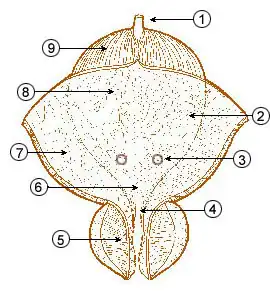

The normal urachus and its anomalous variants

The normal urachus and its anomalous variants -